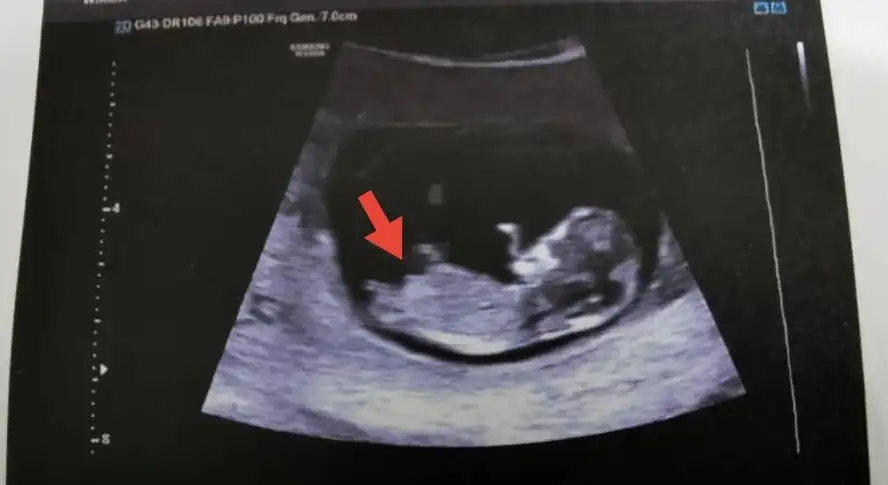

12. haftada karından bakılmıştı. İlk hamilelik. Tahmininiz nedir acaba?

Eklentiler

• 20220508_125823.webp

20220508_125823.webp

28,8 KB · Görüntüleme: 64